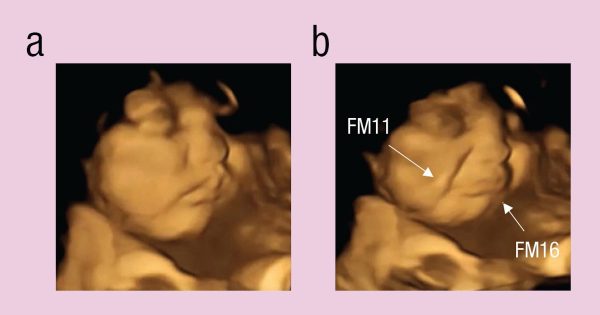

Une étude menée par le laboratoire de recherche fœtale et néonatale de l’université de Durham, au Royaume-Uni, a obtenu des résultats surprenants qui confirment cette théorie ; grâce à des échographies 4D, on a obtenu des images tridimensionnelles animées qui, en temps réel, montrent la réaction des fœtus lorsqu’ils goûtent des saveurs dans l’utérus.

Les experts ont remarqué deux réactions distinctes sur le visage des fœtus : ceux qui ont goûté à la carotte ont laissé entrevoir un sourire, tandis que ceux qui ont goûté au chou ont affiché une grimace de désaccord, comme s’ils étaient au bord des larmes.

Les fœtus du groupe témoin, qui, comme nous l’avons dit, n’avaient été soumis à aucun goût, ne présentaient aucune expression particulière.